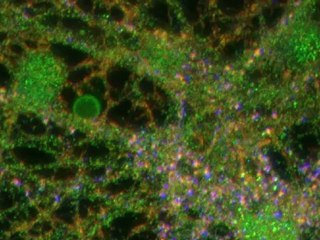

Emisión Especial 2021:br br ¿Has vis­to a una per­so­na que de pron­to pier­de el co­no­ci­mien­to y tie­ne mo­vi­mien­tos brus­cos? Tal vez se tra­te de un tipo de cri­sis epi­lép­ti­ca.